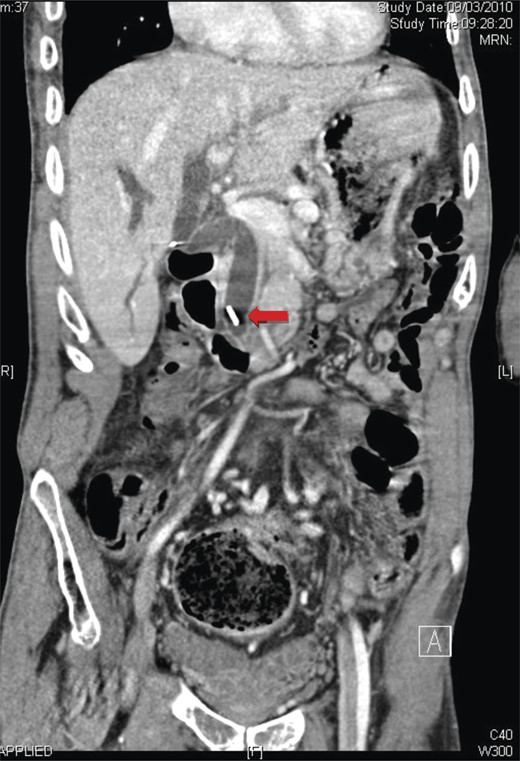

Laboratory tests revealed elevated liver function tests: ALP 285 U/l, ALT 465 U/l, GGT 669 U/l with a normal bilirubin. Magnetic resonance cholangiopancreatography demonstrated marked dilatation of the common bile duct to 15 mm (Fig. 1). A surgical clip was noted in the distal common bile duct, presumed to have migrated from the cystic duct, which it had been used to close 9 years previously.

A coronal view of magnetic resonance cholangiopancreatography showing the presence of a surgical clip and common bile duct dilatation.